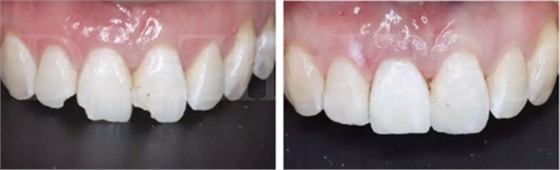

圖16 即刻修復后,患者恢復了美觀

一位年輕女性患者,右上中切牙外傷冠根折2日。

臨床檢查發(fā)現:右上中切牙冠根折,斷面位于齦緣下4到5個毫米。左上中切牙及右上側切牙,切角缺損,牙髓活力正常(圖7)。

治療計劃:微創(chuàng)拔除右上中切牙,拔牙后即刻種植+即刻修復;同期采用雙區(qū)植骨技術。